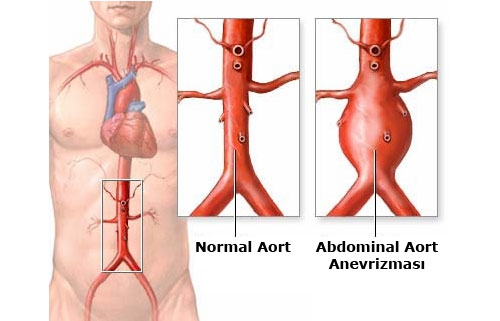

Anevrizma damarların kalıcı olarak genişlemesi veya balonlaşmasıdır. Anevrizma en sık vücudun en büyük atardamarı olan aortada gelişir. Anevrizma zamanla daha da genişler ve tedavi edilmediği takdirde patlar ve çoğunlukla ölüme neden olur. Çoğu kez anevrizmalar bir şikayete neden olmaz ve tesadüfen başka nedenlerle yapılan incelemelerde fark edilir Anevrizma erkenden teşhis edildiğinde kalıcı tedavisi mümkündür. Anevrizmanın klasik tedavisi ameliyat ile genişlemiş damar bölümünün suni bir damar ile değiştirilmesidir. Daha az rahatsızlık verebilecek bir başka tedavi yöntemi ise özel bazı kateterler ile damarın içine girilip, anevrizmanın olduğu damar bölümüne içerden suni damarın yerleştirilmesidir.

Anevrizma damarların kalıcı olarak genişlemesi veya balonlaşmasıdır. Anevrizma en sık vücudun en büyük atardamarı olan aortada gelişir. Anevrizma zamanla daha da genişler ve tedavi edilmediği takdirde patlar ve çoğunlukla ölüme neden olur. Çoğu kez anevrizmalar bir şikayete neden olmaz ve tesadüfen başka nedenlerle yapılan incelemelerde fark edilir Anevrizma erkenden teşhis edildiğinde kalıcı tedavisi mümkündür. Anevrizmanın klasik tedavisi ameliyat ile genişlemiş damar bölümünün suni bir damar ile değiştirilmesidir. Daha az rahatsızlık verebilecek bir başka tedavi yöntemi ise özel bazı kateterler ile damarın içine girilip, anevrizmanın olduğu damar bölümüne içerden suni damarın yerleştirilmesidir.

Anevrizma damarların kalıcı olarak genişlemesi veya balonlaşmasıdır. Anevrizma en sık vücudun en büyük atardamarı olan aortada gelişir. Anevrizma zamanla daha da genişler ve tedavi edilmediği takdirde patlar ve çoğunlukla ölüme neden olur. Anevrizmadan ölüm toplumda ölüm nedenleri arasında 13. sıradadır.

Anevrizma erkenden teşhis edildiğinde kalıcı tedavisi mümkündür. Ancak genelde anevrizmalar pek fazla şikayete neden olmadığı için çoğu kez yapılan incelemelerde tesadüfen saptanır. Anevrizmaların önemli bir kısmı doktor muayenesi ile belirlenebilir. Ancak anevrizma tanısında en basit yöntem ultrasonografidir. Ultrasonografi anevrizmaların tanısında basit, hızlı, ucuz ve güvenilir bir yöntemdir. Ultrasonografi ayrıca toplumda anevrizmalar için çok iyi bir tarama aracıdır. Altmış beş yaşın üzerindeki bütün erkeklerin hayatlarında en az bir kez ultrasonografi ile anevrizma yönünden değerlendirilmeleri gereklidir.

Anevrizmanın varlığı her zaman ameliyat anlamına gelmez. Ameliyat kararı anevrizmanın çapı ve hastanın şikayetlerine göre alınır. Anevrizmanın çapı tedavinin zamanlamasını belirleyen en önemli faktör olup, anevrizma büyüdükçe rüptür riski artar. Bu nedenle 5.5 cm den küçük anevrizması olup ta şikayetli olmayan hastalarda ameliyat gerekmezken, anevrizmanın en geniş çapı 5.5 cm yi aştığında (yaklaşık iri bir limon kadar) artık ameliyat gereklidir. Daha küçük anevrizmalar ağrı yapıyorsa yada aralıklı yapılan ölçümlerde anevrizma hızlı büyüyorsa ameliyat gerekebilir.